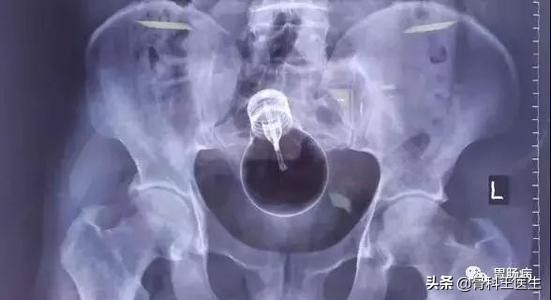

下图你们知道是什么吗?王医生羞羞的表示并不认识:

不认识就不发了,我们发一些认识的: